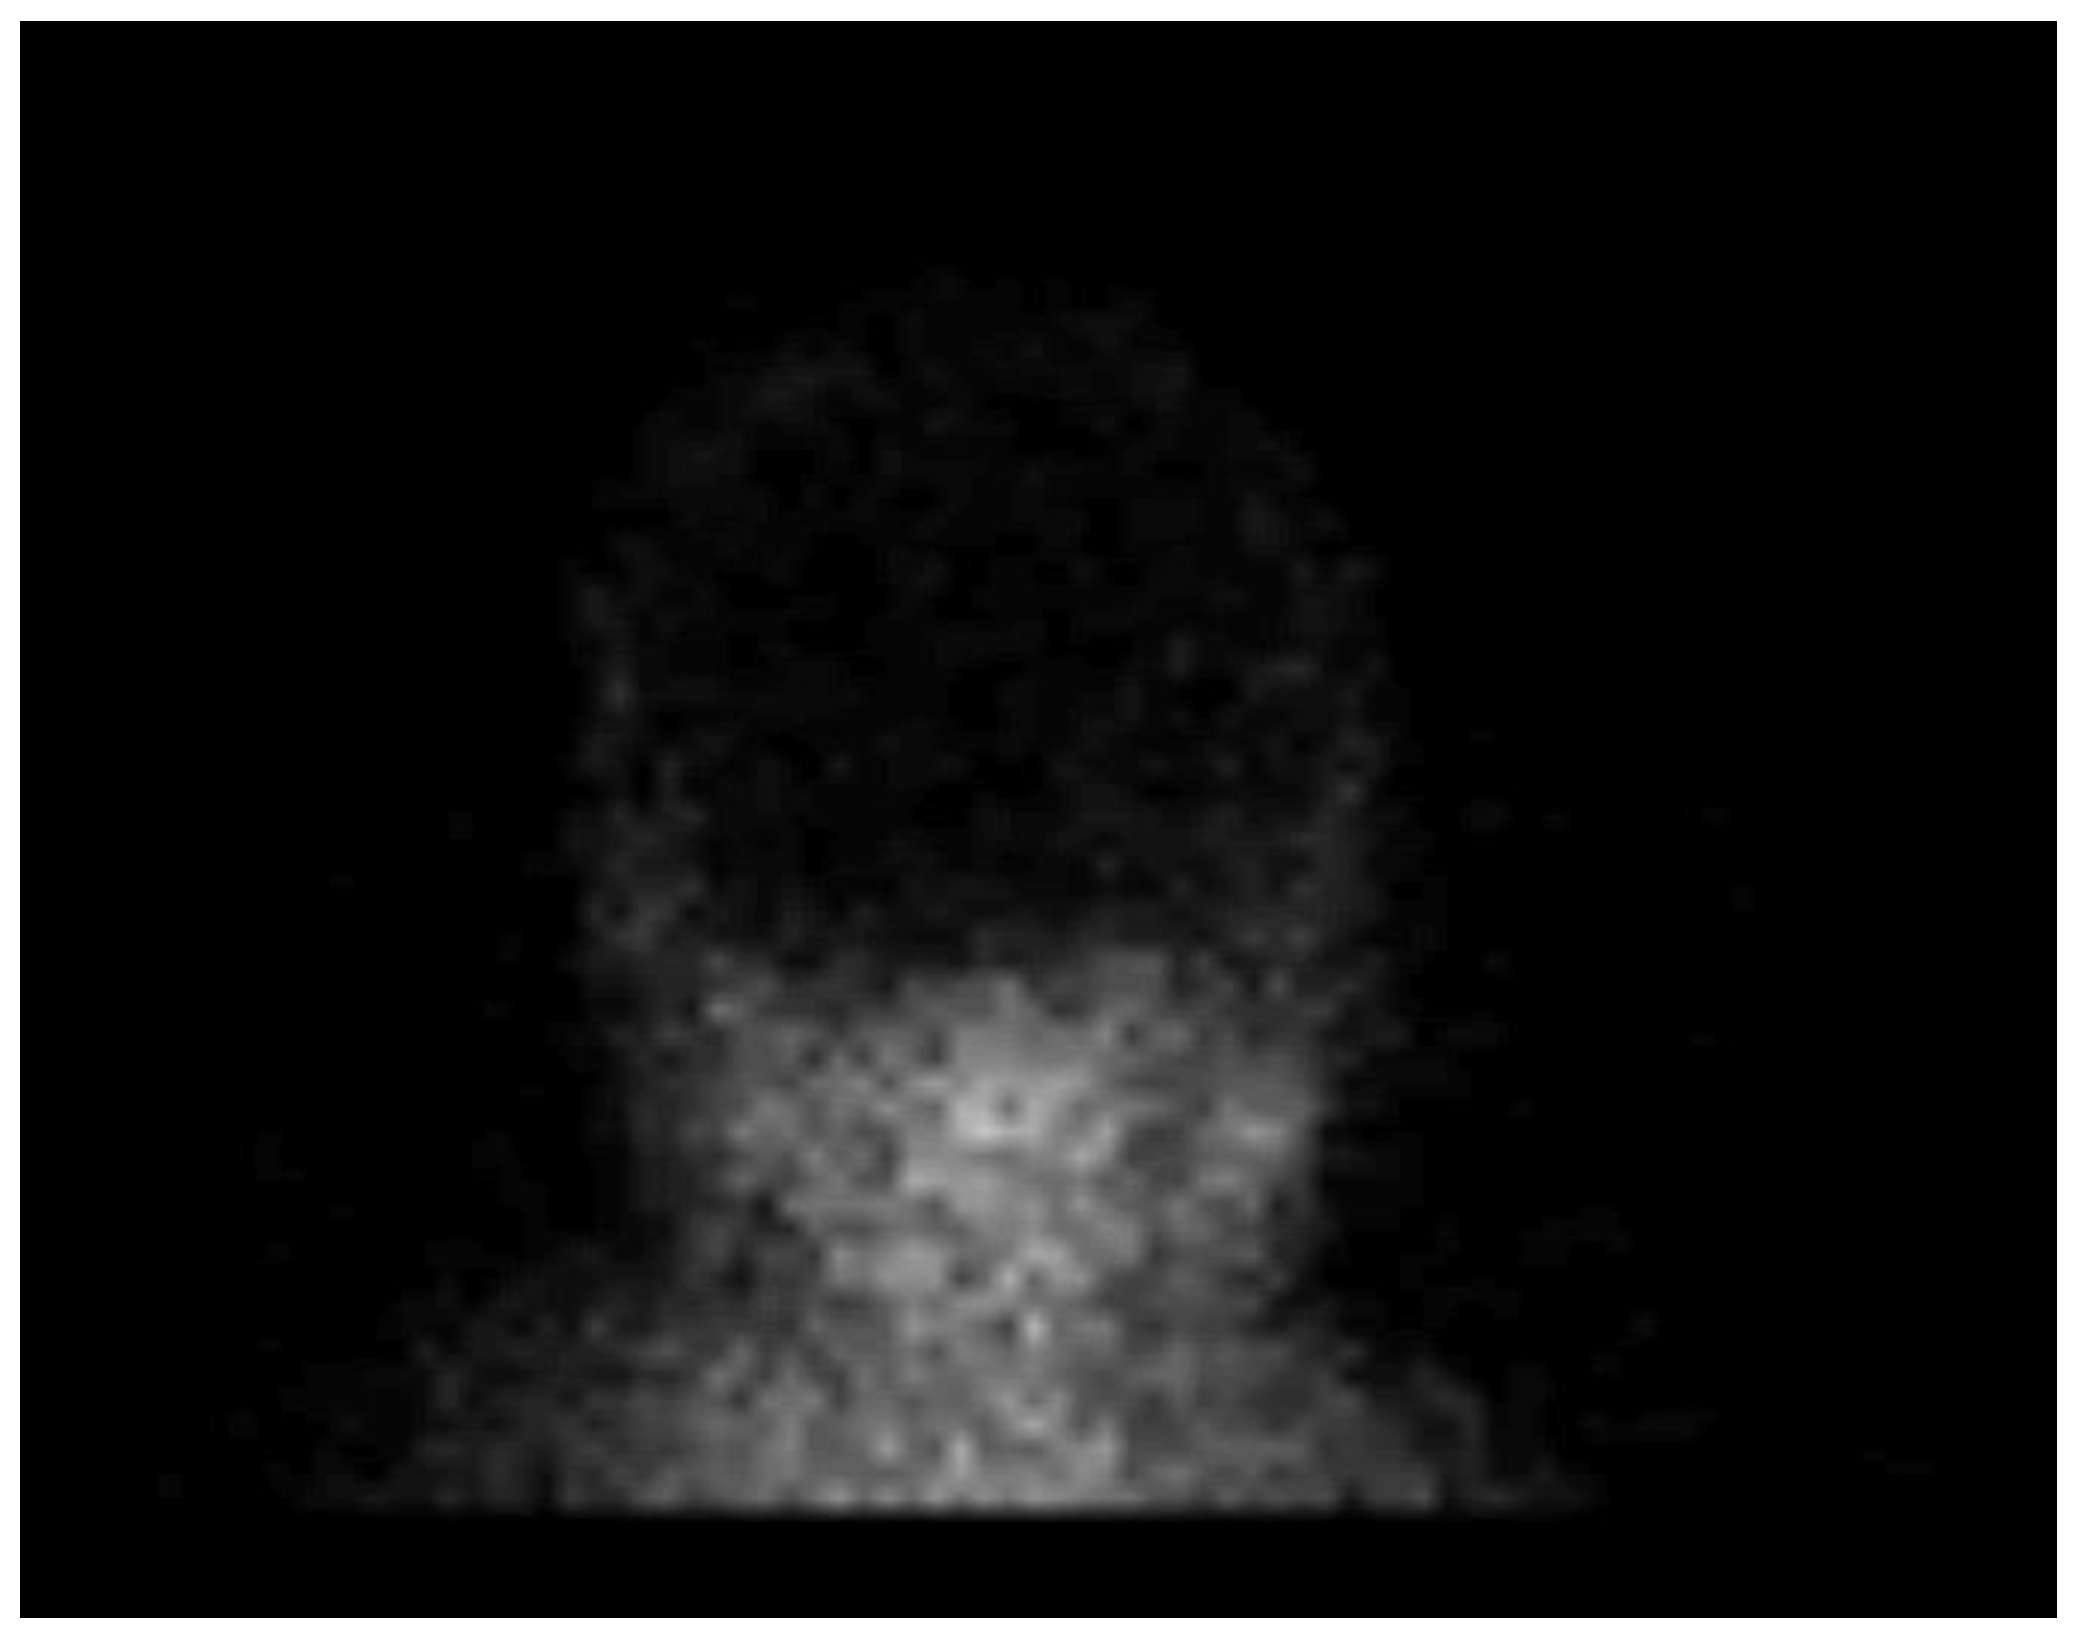

After the US examination, cerebral perfusion scintigraphy was performed as a widely accepted ancillary imaging test for brain death confirmation. The perfusion scintigraphy showed no accumulation of the radionuclides in the brain or the brainstem (Figure 4).

Figure 4. Radionuclide brain scan in the 1-year-old infant. Brain scintigraphy shows the absence of cerebral perfusion in supratentorial and infratentorial areas consistent with the diagnosis of brain death.